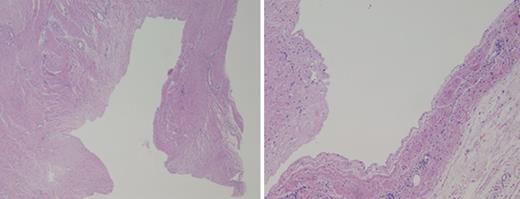

Chest magnetic resonance imaging delineated a large cystic mass extending from the level of the lower neck to just above the level of the diaphragm measuring 11 cm transversely, 4.5 cm anteroposteriorly and 23 cm craniocaudally (Fig. 1).

(Left) Chest CT scan shows the large cystic mass (arrow) between the left posterior ribs and muscles of the left back and scapula. No solid or enhancing components are identified. (Right) Chest MRI shows the large cystic mass extending from the level of the lower neck to just above the level of the diaphragm.